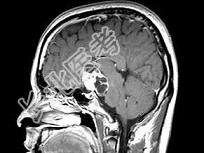

- 单项选择题男,27岁, 头痛、双眼视力下降、多饮、多尿4个月,根据所提供图像, 最可能的诊断是 ( )

A、颅咽管瘤

B、垂体瘤

C、生殖细胞瘤

D、胶质瘤

E、神经鞘瘤